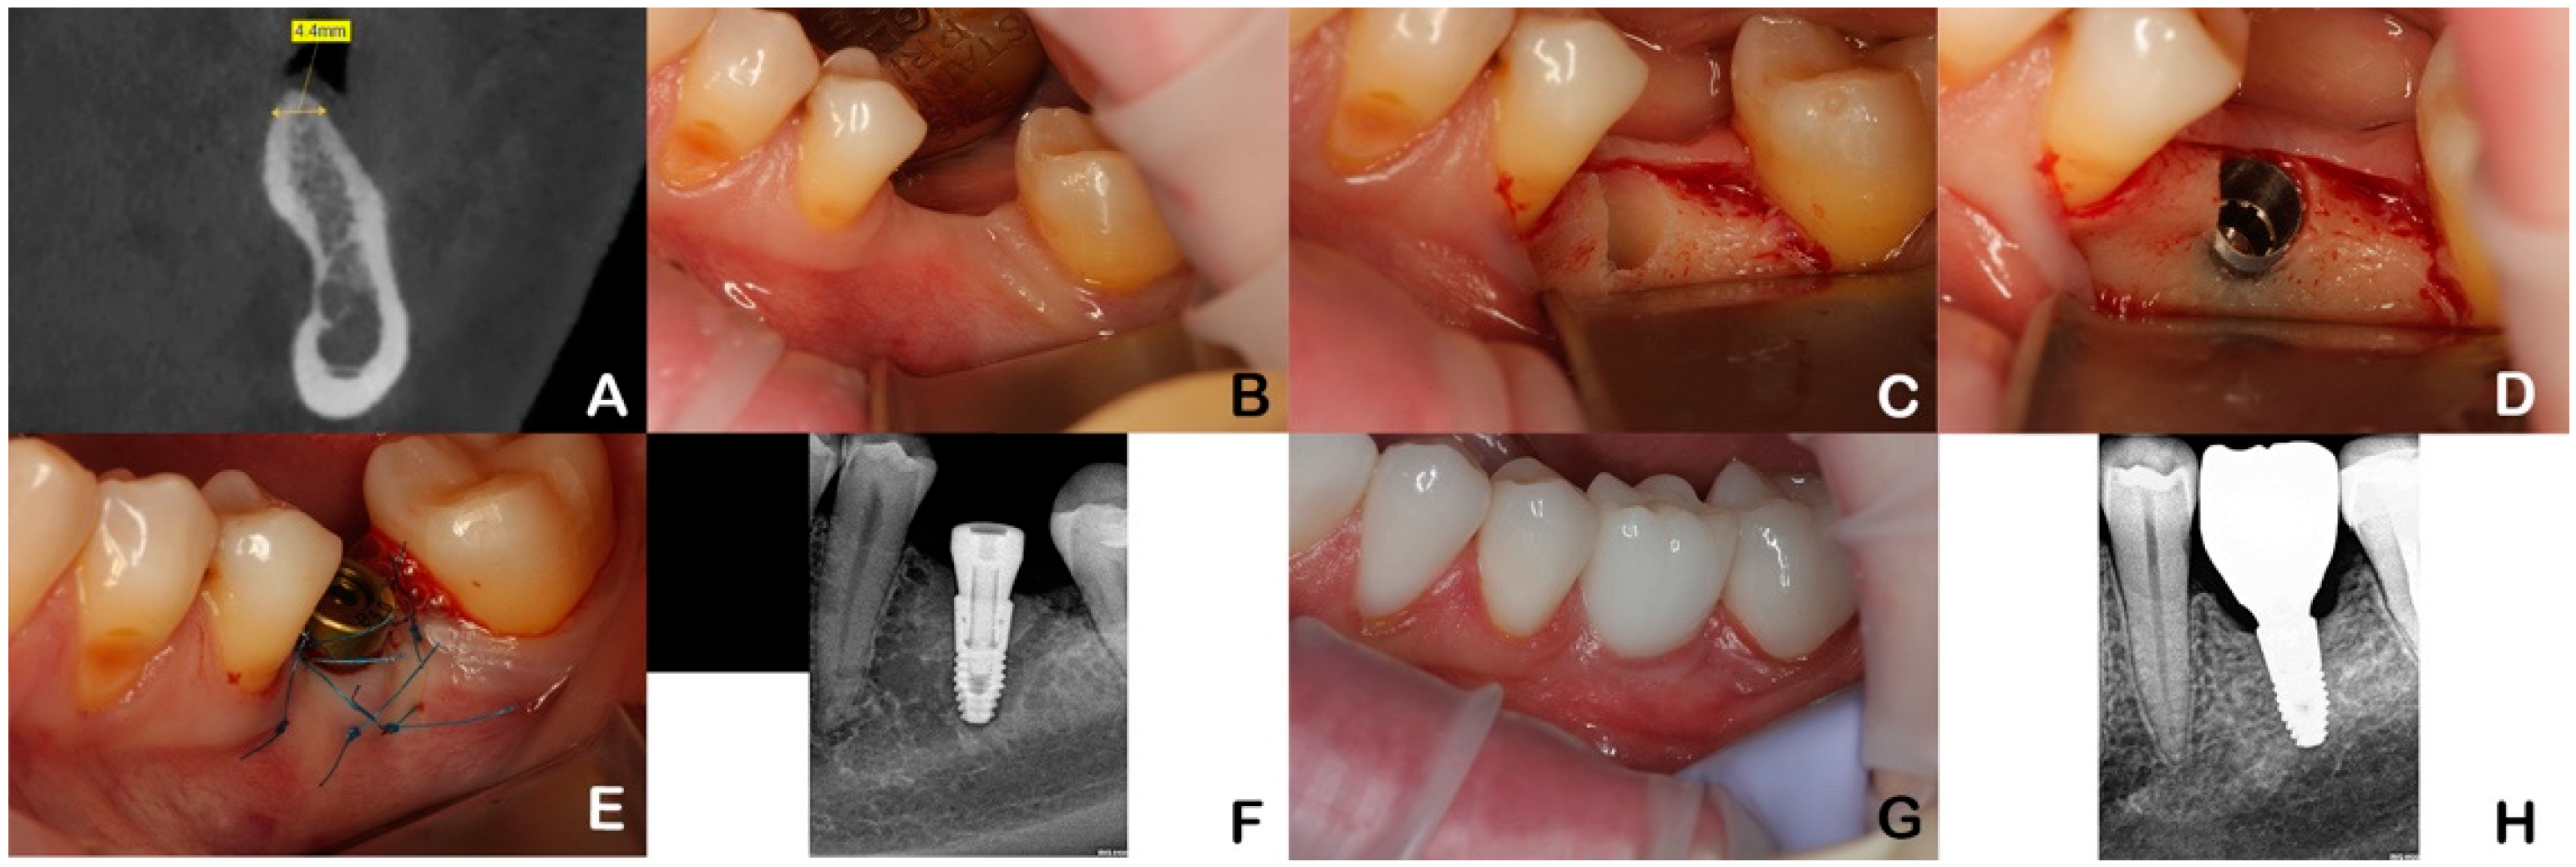

All patients were examined and operated on by one oral surgeon. After infiltration anesthesia, an incision was made in the middle of the alveolar ridge in the area of the missing tooth, and a full-layer mucosal–periosteal flap was removed. Then, the patients of the test group (SLP) received an implant with a sloped platform edge (Astra Tech Osseospeed EV Profile, Dentsply Sirona, Charlotte, NC, USA) according to the manufacturer protocol and a healing abutment. The mucosal–periosteal flap was sutured with Prolene 6.0 suture material (Johnson & Johnson, New Brunswick, New Jersey, USA) without tension around the healing abutment. After 3 months, the patients were referred to the department of prosthodontics for delivery of the final fixed dental prosthesis (Figure 1).

Figure 1.

Case illustrating a patient in the test group (SPT). (A)—implant planning. (B)—single tooth gap. (C)—formation of implant site (buccal bone deficiency). (D)—implant with sloped platform positioning. (E)—suturing around healing abutment. (F)—RVG (radiovisiography). (G)—6 months post installation of permanent prosthesis. (H)—RVG 6-month follow-up.